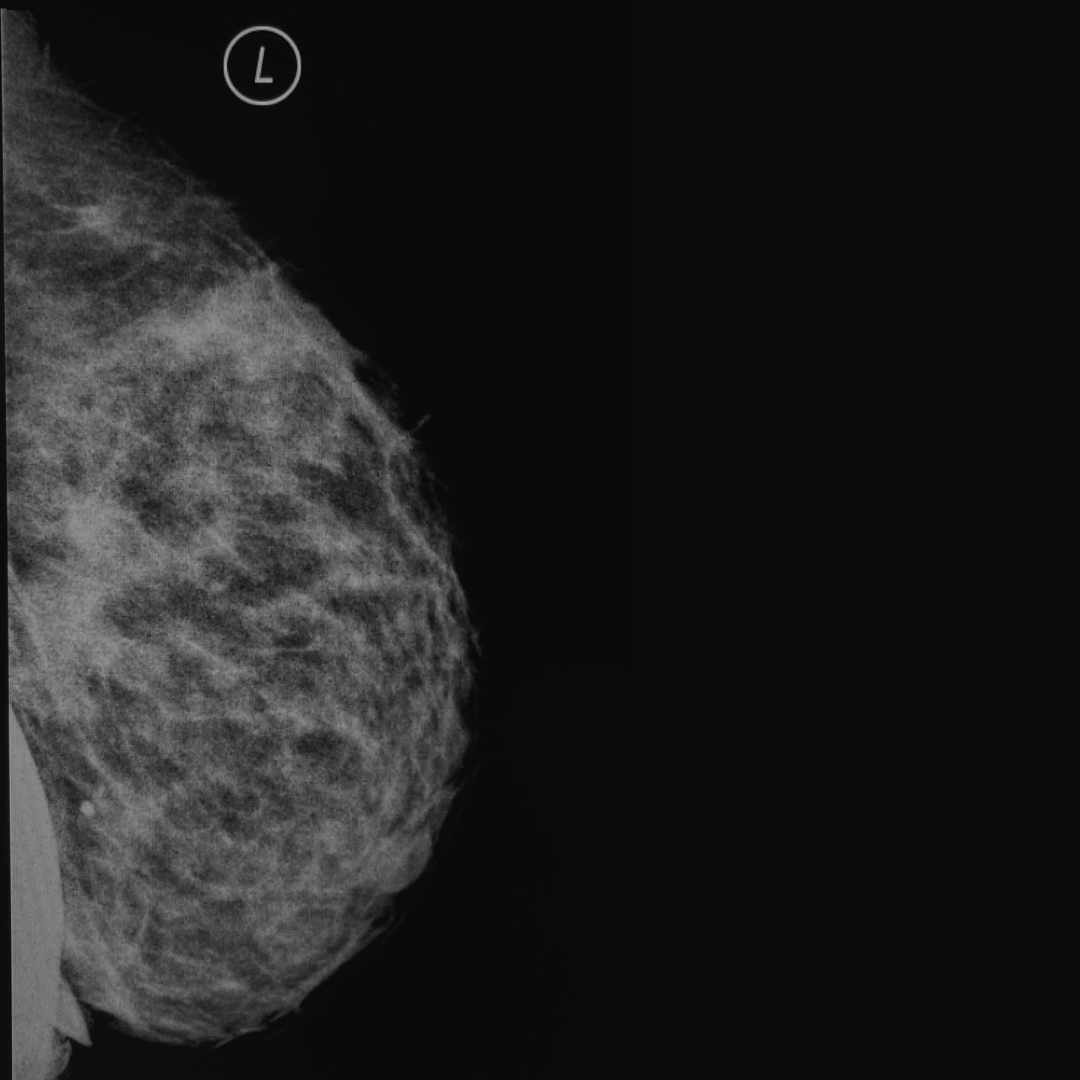

MAMOGRAFÍAS

Detección temprana de cáncer de mama, con equipos modernos y radiólogos expertos:

- Tamizaje

- Diagnóstica